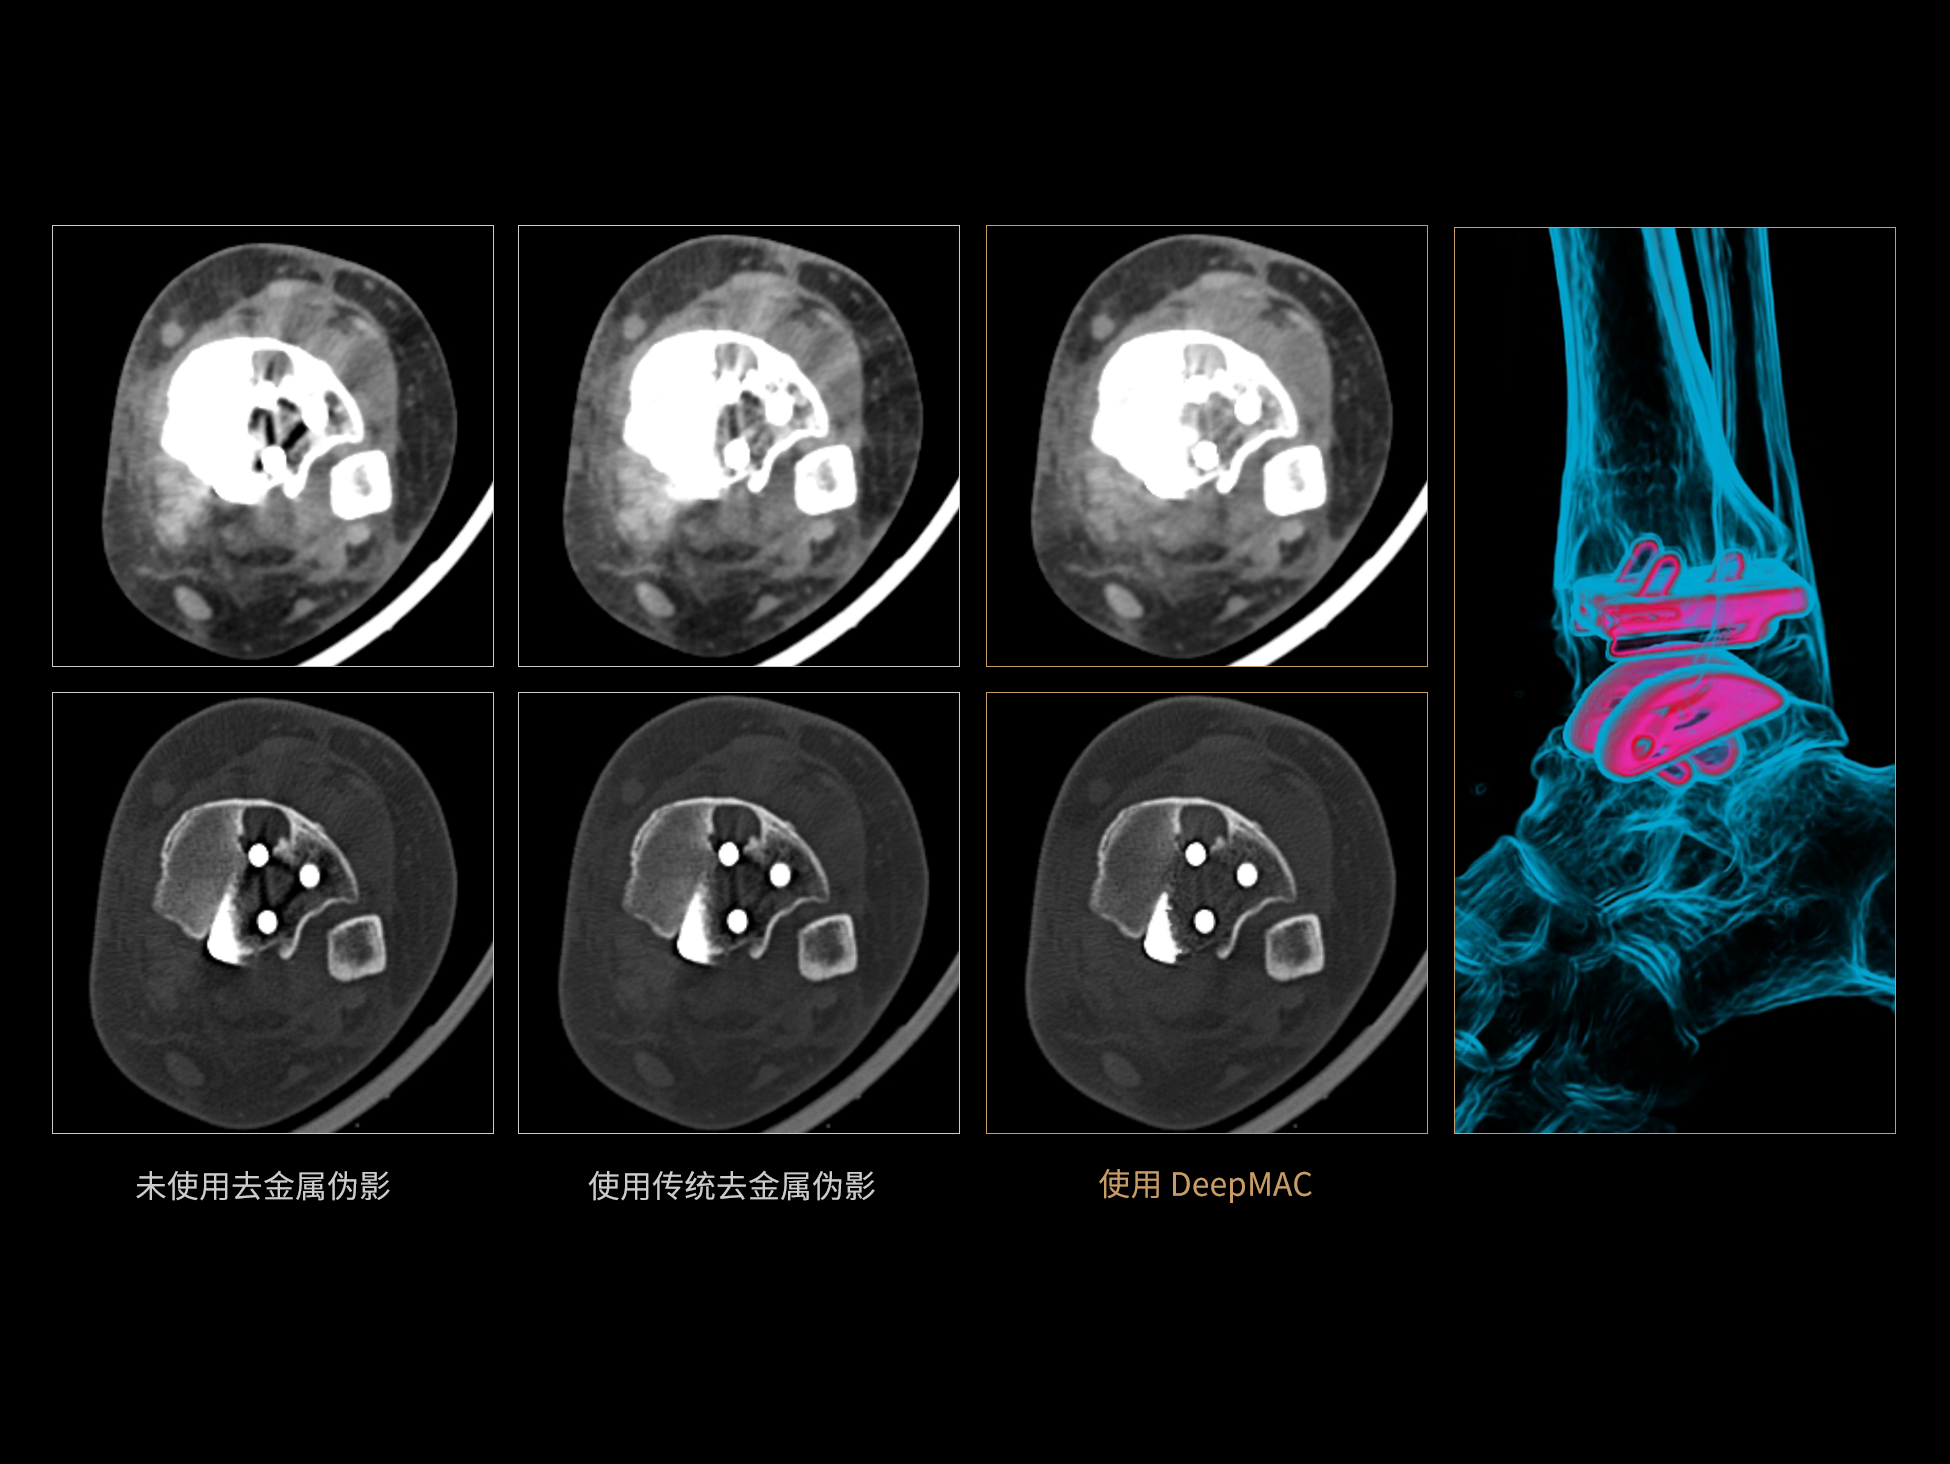

DeepMAC**:AI去金属伪影算法

DeepMAC**智能金属伪影校正技术通过深度学习算法有效解决了临床中各类不规则金属植入物导致的CT成像伪影问题,具备良好的通用性和稳定性。该技术依托大规模、高多样性的训练数据集,覆盖了包括髋关节置换体、脊柱内固定器(胸腰椎/颈椎)、四肢骨科植入物、牙科修复体以及血管介入弹簧圈等在内的金属植入物类型。通过深度神经网络的特征提取与解剖结构重建优化,DeepMAC** 在有效抑制金属伪影的同时,最大程度地保留了真实的解剖细节,显著提升了影像诊断的准确性。

±10HU

CT值准确性※ ※

≥50% 重建速度提升

相较传统算法,重建速度提高50%以上※ ※

** 仅供科研使用

※ ※数据在测试条件下,与传统MAC去金属伪影算法对比获得